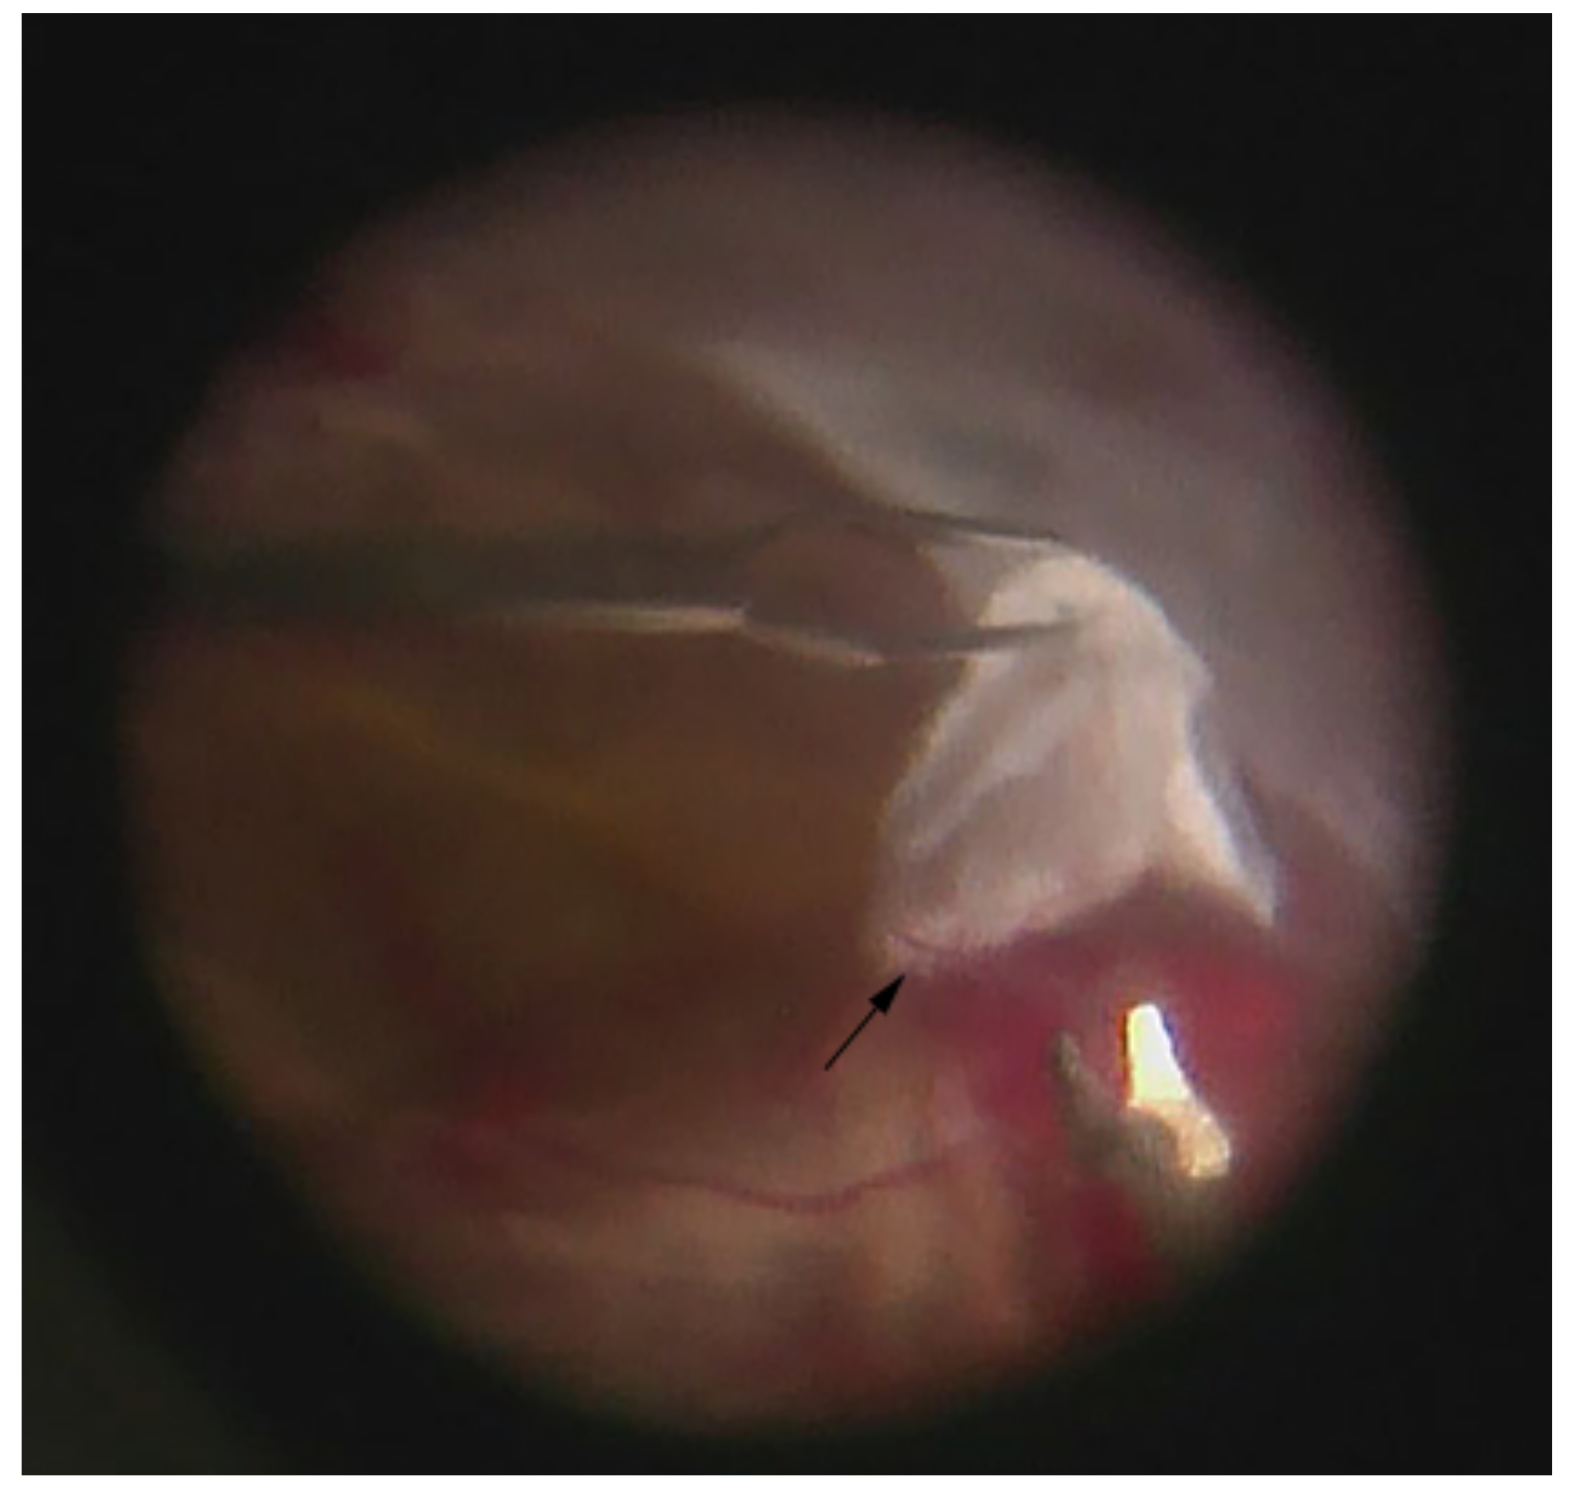

As a whole, the majority of the literature that has studied the vitreous in PDR shows an expected elevated change in the concentration of major and some minor cytokines in active PDR. It is clear that cytokines that play a role in diabetic retinopathy are produced from retinal cells, the retinal pigment epithelium, pericytes, endothelial cells, Müller cells, astrocytes, and hyalocytes [173]. The pathogenesis of diabetic retinopathy cannot be summarized only in the retina. The vitreous can act as a reservoir for these mediators, and this is the reason that eyes that undergo a vitrectomy have long-lasting benefits [174]. The vitreous plays more of a role in the proliferative stage and in membrane formation. Fibrovascular membranes are composed of many cell types, i.e., hyalocytes, fibroblasts, retinal glial cells, macrophages/monocytes, laminocytes, and vascular endothelial cells [175]. The hyalocyte cells which are a component of the vitreous can be a source for connective tissue growth factor (CTGF) and may play a role in the formation of fibrous tissue in the proliferative stage. Hyalocytes not only have a role in the proliferative stage but also in immunological disorders if we consider diabetic retinopathy an autoimmune process. Hyalocytes may have a role for changes in the vitreous body as a source of antibodies [175]. As active PDR changes to early TRD formation (Figure 4), an increase in vitreous pro-fibrotic factors and cytokines within cell types (e.g., stromal, endothelial) in fibrovascular vascular membranes has been shown in multiple studies [36,43,112,171,176].

Figure 4.

Fibrovascular membrane of a tractional retinal detachment (TRD). A combination of forceps and scissors is used to delaminate and remove the membrane from the retinal surface without injury to the retina. Remnant neovascularization (arrow) can be seen at the base of the white fibrous membrane as the majority has regressed following preoperative treatment with bevacizumab. (Intraoperative image courtesy of Siva S.R. Iyer, MD).